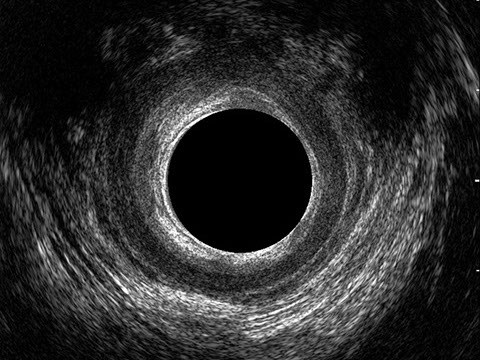

L’ecografia transanale è un esame diagnostico per immagini che consiste nell’introduzione di un trasduttore ad ultrasuoni. Le immagini qualitativamente migliori del canale anale sono ottenute usando un trasduttore rotante, montato in un manipolo rigido, che fornisce un’immagine a 360°. Con le apparecchiature più moderne è anche possibile ottenere immagini tridimensionali.

L’ecografia transanale permette di distinguere la sottomucosa che riveste il canale anale, lo sfintere anale interno, e lo sfintere anale esterno.